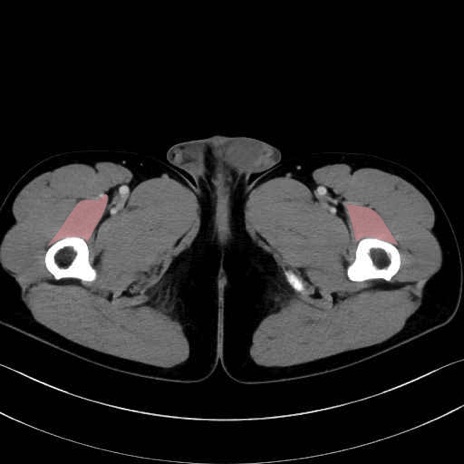

中間広筋 (Vastus intermedius)